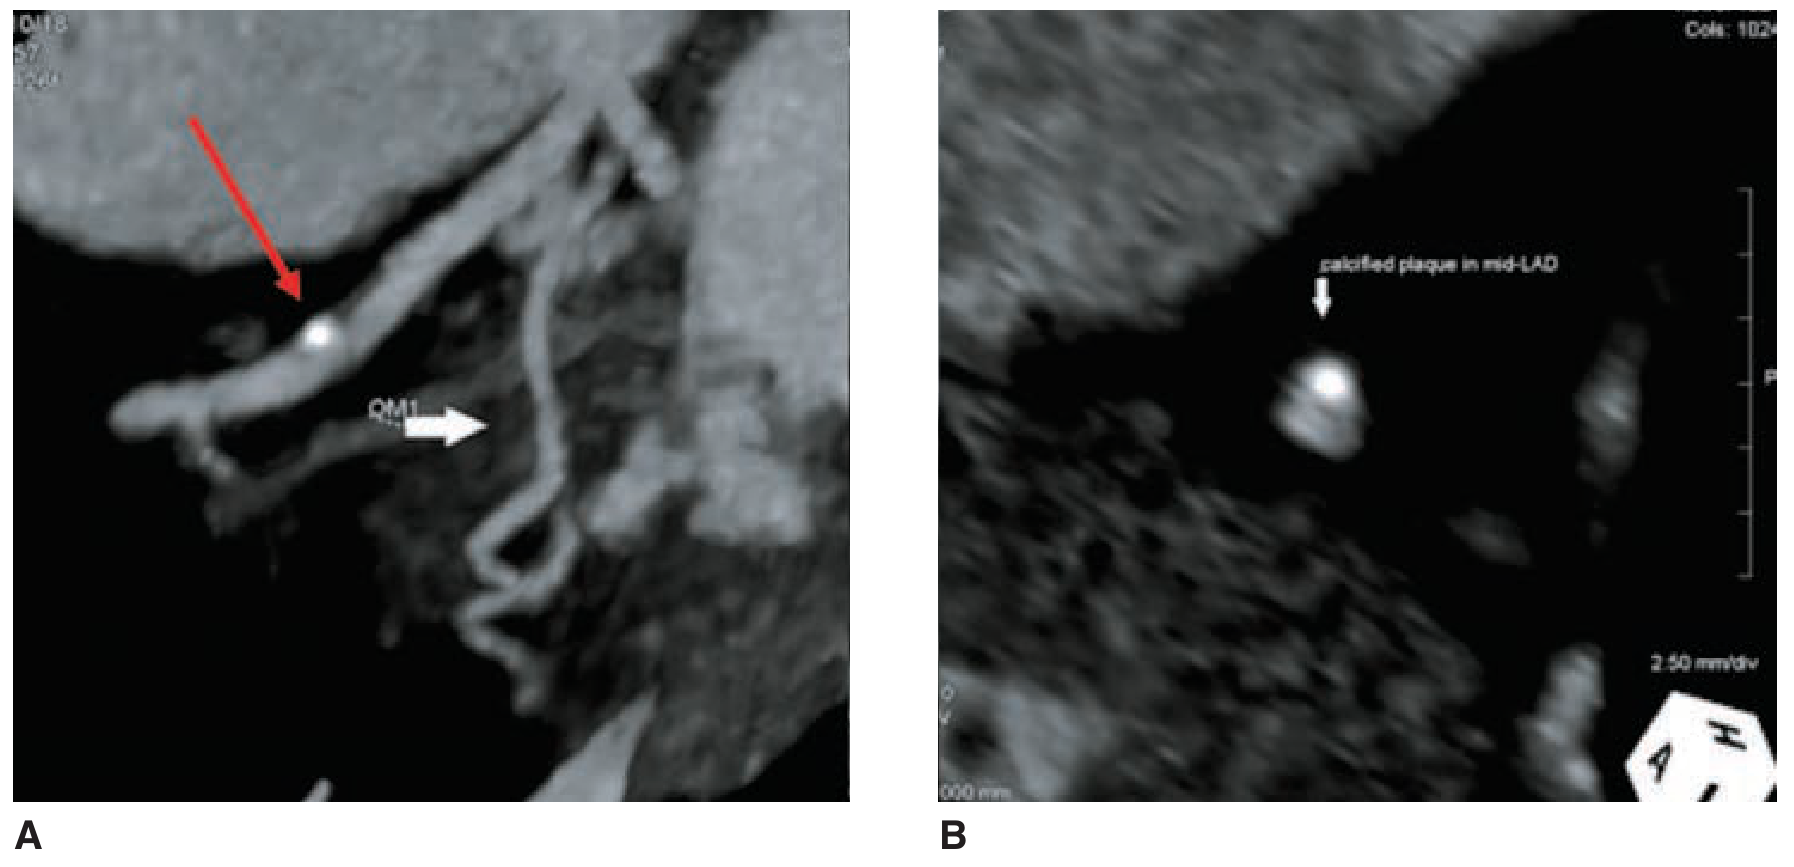

CCTA: A - Longitudinal MIP of mid-LAD showing a calcified plaque (red arrow). B - Axial MPR of the same non-obstructive plaque.

CCTA plaque imaging: Longitudinal MIP (left) showing calcified LAD plaque (red arrow); axial MPR (right) of the same non-obstructive lesion — Fuster & Hurst's The Heart, 15th ed., p. 137